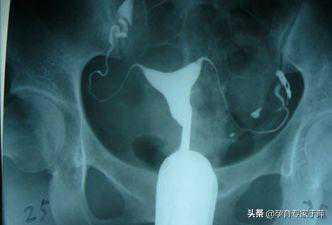

输卵管造影:

月经干净后3-7天内(不同房)进行此项检查。特别是对于第一次做输卵管检查的女性,我还是建议先做输卵管造影检查,造影可以清晰的看到输卵管的形态、子宫的形态、输卵管堵塞的位置,是黏连还是堵塞,还是通而不畅,输卵管造影都可以清晰的看到,以便给医生的对症治疗做出准确的判断。